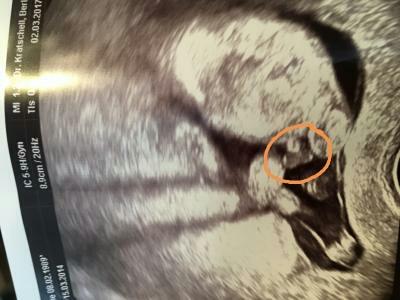

Hey ihr lieben :) war heute bei 14+4 beim Arzt und er meinte er denkt es wird ein Junge. Er hat mir extra das Bild von unten ausgedruckt. Man sehe da die Hoden. Aber ist das nicht zu früh? Erkennt ihr was auf dem Bild? Versuche mal ein Bild anzuhängen. Lg P.s das Bild ist, warum auch immer, nicht so wie ich es fotografiert habe (also verdreht). Hoffe ihr erkennt tzd was ich meine ^^

Oh ja, das sieht man ja ganz deutlich! Bin gerade mit Jungs Nr. 3&4 schwanger und so sah das jedes Mal aus. Die Jungs sind da sehr zeigefreudig. Bei uns hieß es beim Schallen immer: Das Gesicht ist leider verdeckt, aber das Geschlecht könnte ich Ihnen nochmal ganz deutlich zeigen. (Dankendes Abwinken. ) LG Tine

Ich mache nachher noch mal ein US, wo man alles sieht, auch das Datum! Damit du siehst das ich es nicht nötig habe hier fremde Bilder reinzustellen ;) und ich versuche es so reinzustellen; das es richtig rum ist. Man sieht den Bauch, die Beine und am Bauch halt laut Arzt Hoden und Penis.

Den anderen auf jeden Fall schon mal Danke. Bin halt noch immer skeptisch, weil ich sehr unsicher bin. Eher denke es ist die Nabelschnur. Habe einen 3jährigen Sohn, bei dem es anders aussah.

Die Nabelschnur ist es nicht. Sie wäre weiter oben.

Hier eindeutig Penis und Hoden